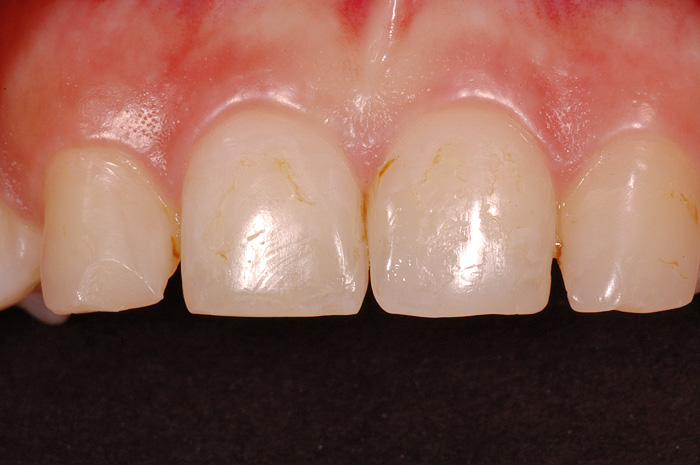

Ist ein Zahn sehr stark oder bis unter das Zahnfleisch zerstört, kann er nicht mehr mit einer herkömmlichen Kunststofffüllung versorgt werden. Der noch vorhandene Restzahn lässt sich nur noch durch eine Krone restaurieren. Sie besteht aus einem individuell gegossenen Metallgerüst, auf welches in mehreren Schichten Keramik aufgebrannt wird oder kann als rein vollkeramische Krone hergestellt werden, was zu einer noch höheren Ästhetik führt.

Die Restauration eines Zahnes mit einer Krone ist aufwendig. In einem ersten Schritt wird Karies und das alte Füllungsmaterial vollständig entfernt und der Zahnstumpf wieder aufgebaut. Eine präzise Abformung der Situation dient dem Zahntechniker als Grundlage für ein Gipsmodell, auf dem er die Krone herstellt. Sofern Farbe und Form perfekt stimmen, kann die Krone in einer zweiten oder dritten Sitzung beim Zahnarzt zementiert werden. Für die Zeit zwischen Präparation des Zahnes und dem definitiven Zementieren der Krone wird der Zahn mit einem individuell hergestellten Provisorium versorgt.